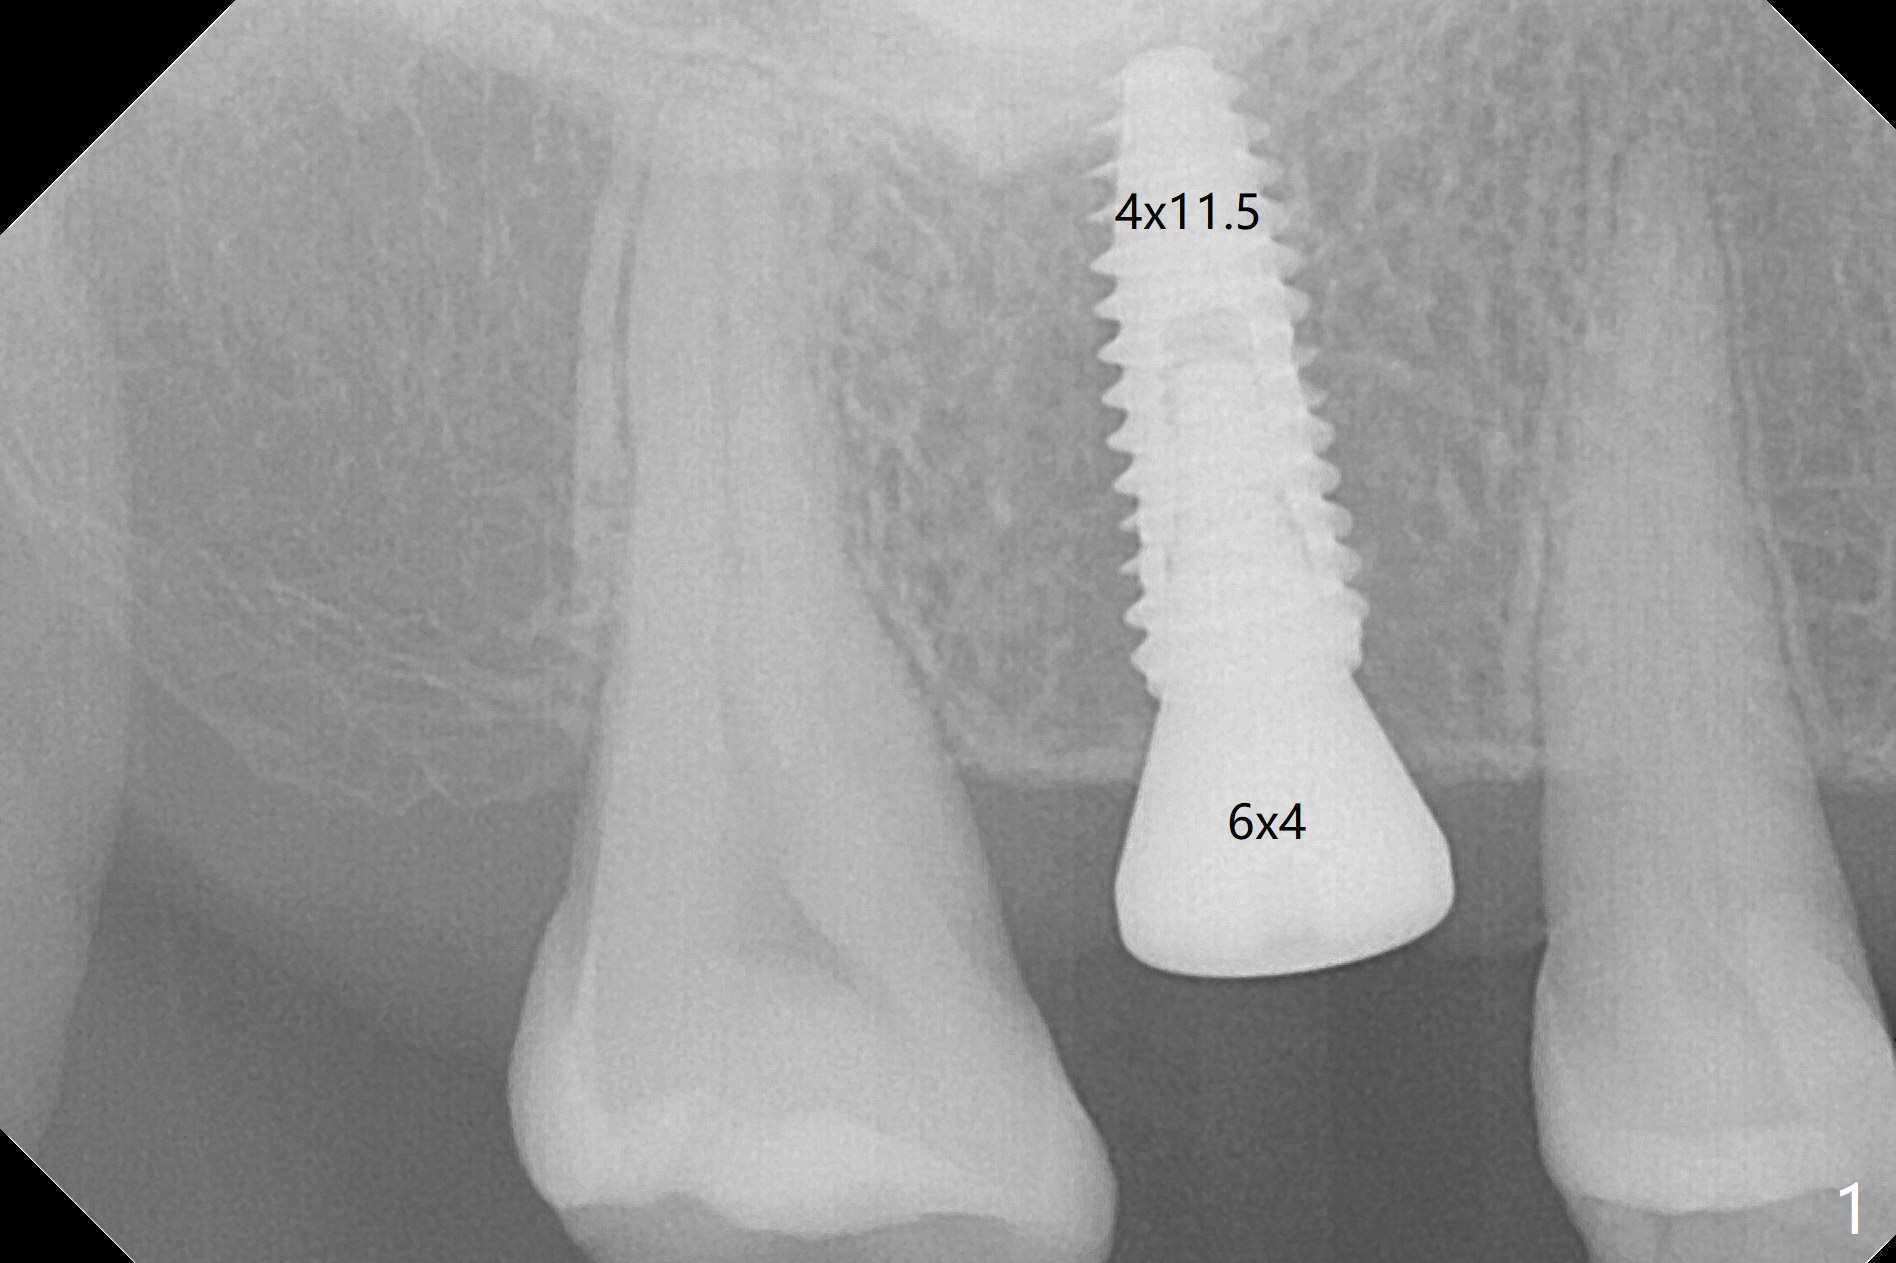

With understanding tissue punch and engagement of drill as much as possible into guide sleeve before pressing pedal, guided surgery is accomplished with confidence (Fig.1,2).  With undersized drilling, there is no thread exposure palatally, when a flap is raised.  Vanilla graft is placed, since it has been prepared before incision.  No membrane is used.  It appears that the palatal bone expands while the implant is being placed.  CBCT taken 10 days postop shows apparently the coronal end of the palatal plate (Fig.3 arrows) and bone graft (<).  Although postop pain is slightly more associated with incision for bone graft, the wound heals with periodontal dressing 10 days postop.